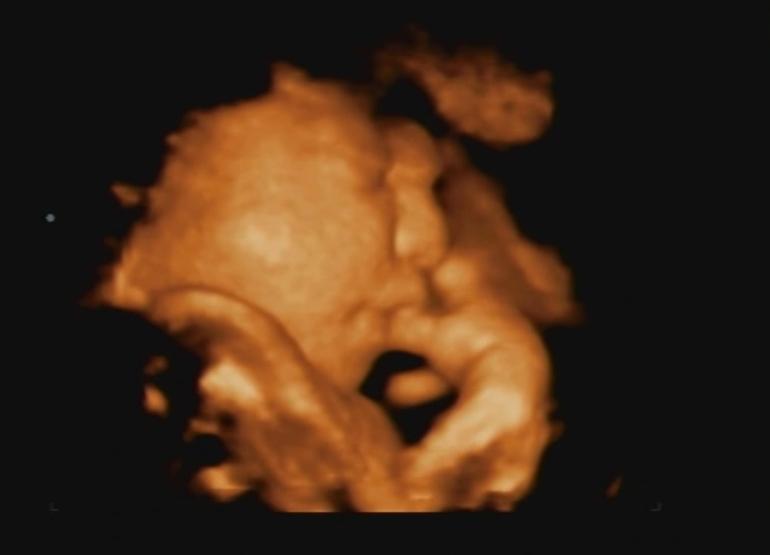

Мои неделькиИтак, идет 32 неделя беременности. Успешно вхожу в состояние "когда же уже". Ходили на УЗИ, ахнула от размера щек детеныша, сразу вспомнила анекдот "Тимофей, втяни щечки, не проходим". А вообще приятно наблюдать, как он там барахтается, причмокиваем, зевает, пальчик сосет. Про себя подумала, хорошо что купила таки авентовское пустышки, чую пригодятся. Муж испугался, что у ребенка хобот, который на самом деле оказался ручкой у лица. Но забавно, да.

Ниже фото сына с пальцем во рту, фото моих попыток остановить растущий вес и то, как муж собирал шкаф из икеи. Я помогала)